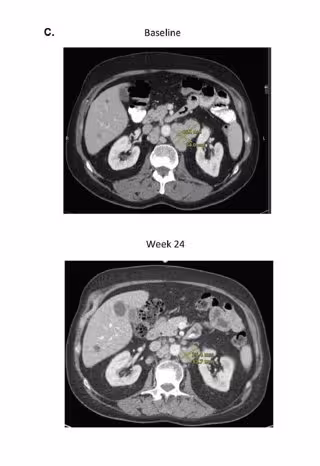

Una vez pasado el tiempo de estudio, los científicos observaron que el 13 por ciento de los hombres experimentaron una disminución en el nivel de antígeno prostático específico (PSA) de, al menos, el 50 por ciento. Asimismo, una cuarta parte logró una respuesta objetiva, lo que significa que sus tumores se contrajeron parcial o completamente con la inmunoterapia combinada durante unos nueve meses.